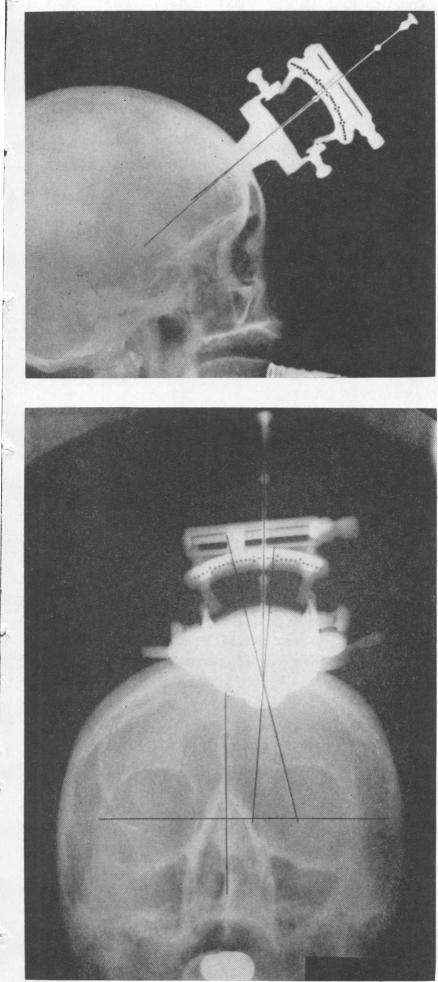

STEREOTACTIC TRACTOTOMY IN THE SURGICAL TREATMENT OF MENTAL ILLNESS.

J Neurol Neurosurg Psychiatry. 1965 Aug;28(4):304-10. doi: 10.1136/jnnp.28.4.304.